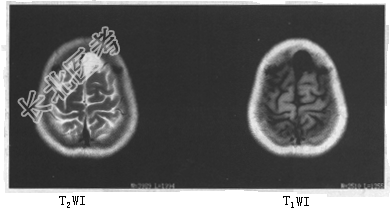

- 单项选择题患者女,49岁。头痛, MRI表现如下图,最可能的诊断是

A、硬膜下血肿

B、硬膜下积液

C、Dandy-Walker综合征

D、脑积水

E、蛛网膜囊肿